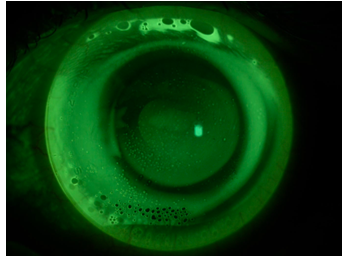

Following the execution of the corneal topography, the subject presents the parameters of curvature and size of the iris visible for the left eye, listed in the following Table 1. From the application protocol, the trial set lens applied is the one with 7.94 mm BOZR, PC unchanged compared to the BOZR and DT of 14.00 mm. The fluorescein pattern after 2 hours of wearing, shown in Figure 1, shows that there is excessive lifting in the central optical zone, so much so that the fluorescence, by gravity, settles downwards. In the pericheratic area, a too closed tear reservoir is generated, which assumes an inverse hourglass shape, due to the astigmatism against the rule of the subject's cornea.

Figure 1 Fluorescein pattern of the lens with BOZR 7.94 PC 0.00 DT 14.00 in the left eye after 2 hours of wearing.